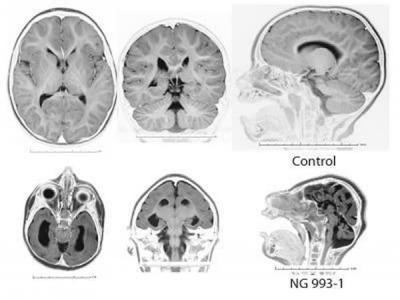

单个基因突变影响人类大脑皮层演化

上图为正常人 下图为严重头小畸形 人类的演化非常重要的特征就是我们大脑的演化...